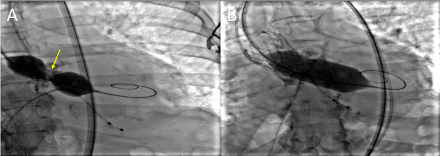

Case Description: An 80-year-old woman with history of hypertension, HFpEF, and TAVR 8 months prior for severe aortic stenosis (AS) at an outside hospital presented with worsening dyspnea and peripheral edema over the past month. Blood pressure was 148/53mmHg, heartrate 83bpm, oxygen saturation 98% and auscultation revealed a harsh holosystolic murmur 4/6 loudest at left sternal border and bibasilar rales. Chest X-ray showed pulmonary edema and bilateral pleural effusions. NT-proBNP was 17,000pg/ml and troponin-I was negative. Echocardiogram showed EF55-60%, a membranous VSD, severe pulmonary hypertension, and moderate paravalvular leak (PVL). Coronary angiogram showed non-obstructive disease. Right heart catheterization confirmed significant left to right shunting.

Treatment/Outcomes: Cardiothoracic surgery was consulted for multidisciplinary evaluation, and joint recommendation was for surgical aortic valve replacement and VSD closure which was successfully performed. One month follow-up echocardiogram showed normal aortic valve gradient without PVL and normal right ventricular pressure.

Discussion/Conclusion: Numerous potential risks such as severe and uneven calcification of the native valve, an elliptic aortic annulus, excessive valve sizing, or elevated valve placement can lead to VSD. A recurrent element in many of these instances involves direct trauma to the septum caused by the implanted valve, exacerbated by subsequent annulus dilation. The presence of PVL is common post-TAVR and is an established independent prognostic factor, while VSD post-TAVR is uncommon, but may be associated with low implantation position relative to the aortic annulus or post-implantation balloon dilatation. Rarely, worsening VSD may require operative management. In this case, the improvement of heart failure symptoms and echocardiogram parameters after transthoracic surgery confirmed successful repair.